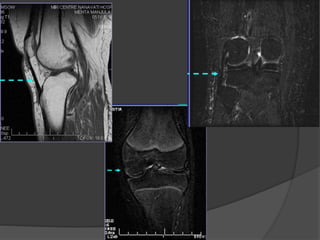

Colocado y centrado el paciente, comienza la secuencia de

localización. Dando imágenes en los tres planos: axial,

sagital y coronal

axial

sagital coronal

Metodología Colocado y centradoel paciente, comienza la secuencia de localización. Dando imágenes en los tres planos: axial, sagital y coronal axial sagital coronal